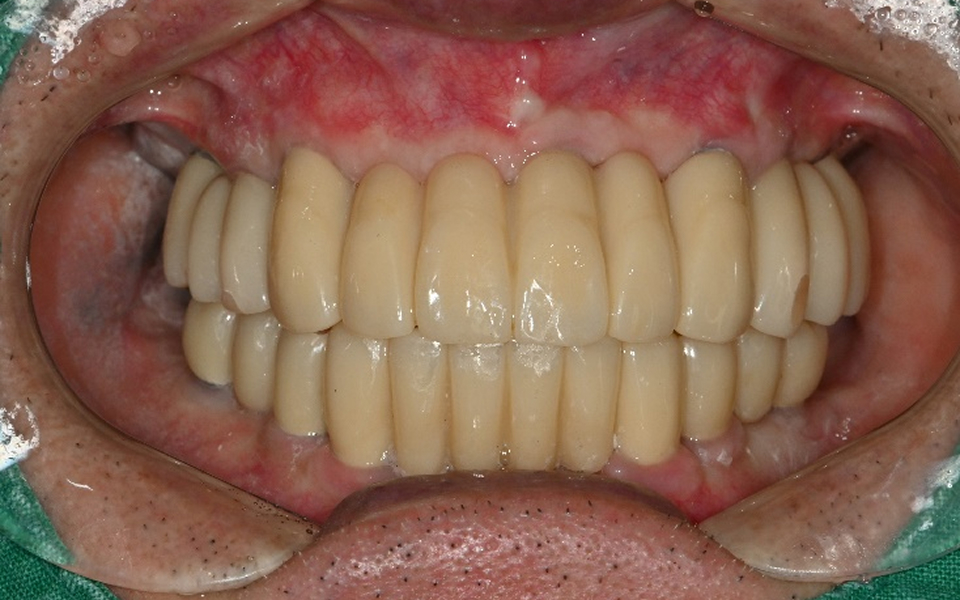

바른선택치과의원 전악 임플란트

before after

치료 시작 전 촬영 2024.01.24 | 치료 완료 후 촬영 2024.12.26

CASE 01 김** / 60대

전악임플란트

3 고정성 보철물로 수복 후 일상 회복